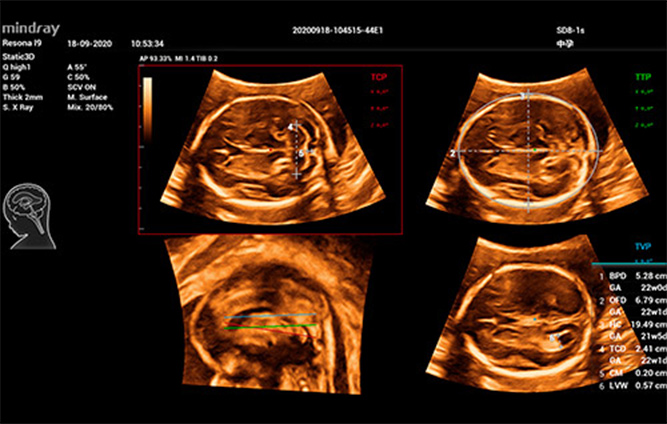

Smart Planes CNS

Smart ICV: CƔlculo automƔtico del volumen intracraneal

Para reducir la dependencia del usuario y mejorar la eficiencia del diagnĆ³stico, Mindray desarrollĆ³ una innovadora interacciĆ³n 3D/4D basada en situaciones clĆnicas para contextos tĆpicos de exĆ”menes de ecografĆa 3D (como los del cerebro, el rostro, la columna vertebral y los huesos largos del feto). Esta soluciĆ³n permite la identificaciĆ³n automĆ”tica de escenas, la optimizaciĆ³n automĆ”tica de las imĆ”genes, la captaciĆ³n automĆ”tica de planos y la cuantificaciĆ³n automĆ”tica con un solo clic. Realmente hace posible un flujo de trabajo automĆ”tico durante todo el procedimiento, lo que otorga una fuerte confianza en el diagnĆ³stico para una mejor atenciĆ³n del paciente.